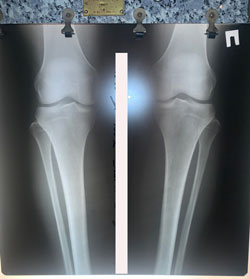

Исходник - 36 лет.

Дата операции - 02.12.2020

Ещё раз: невозможно устранить варусную деформацию при помощи круропластики

Очередной пример!

после удаления имплантатов